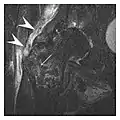

Figure 1: A 56-year-old woman presenting with left knee pain after a fall. (a) Initial anteroposterior radiograph was considered normal, however, subtle cortical disruption of the anterior rim of the medial tibial plateau, medial to the tibial spine, is noted (arrow). (b) Coronal T1-weighted MRI confirms the cortical disruption (arrow) and shows extensive fracture through the proximal tibia. (c) Coronal proton density-weighted image with fat saturation shows extensive edema in the subchondral bone. Note also hypersignal adjacent to the medial collateral ligament corresponding to a grade I sprain (arrowheads).[1]